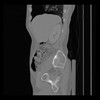

36 CUERPO,CE,Sagittal,3.000,CUERPO,Sagittal,